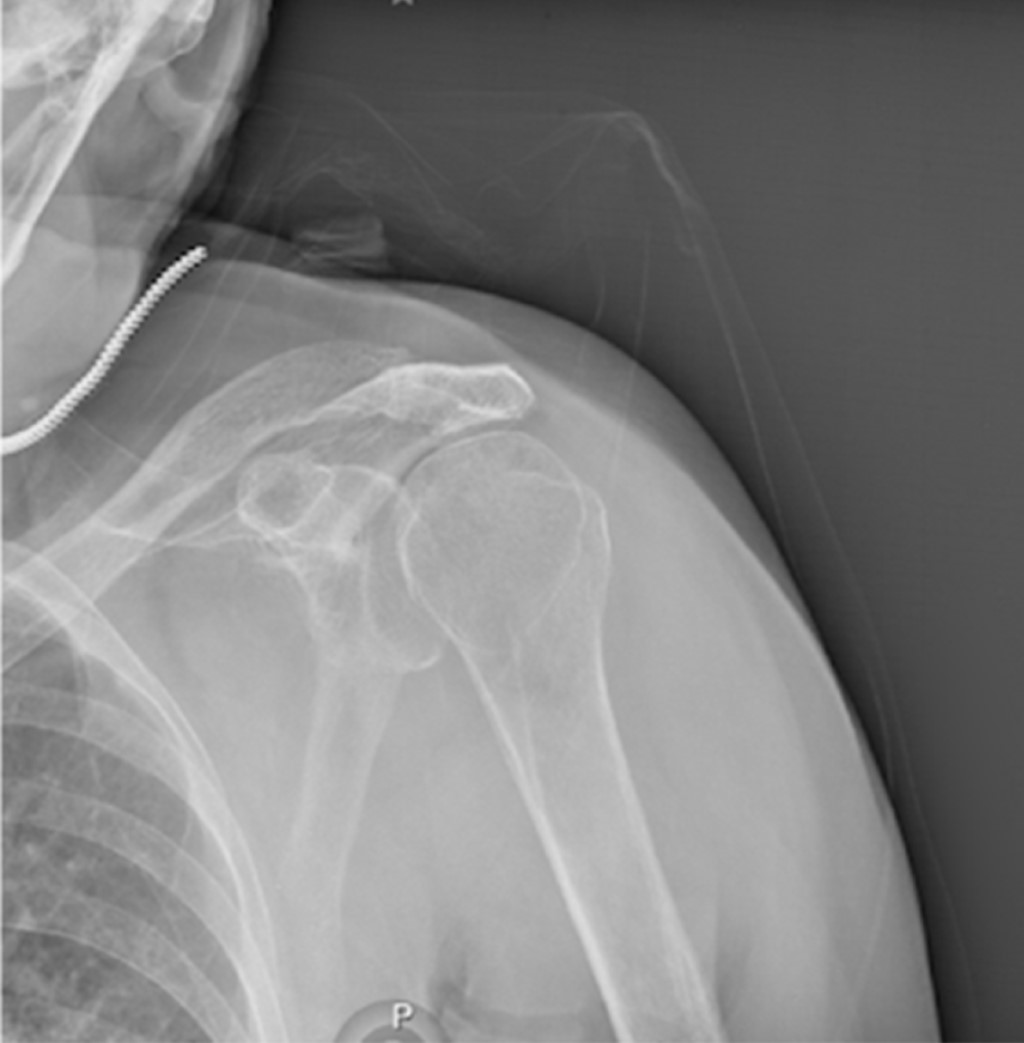

Paciente femenino de 86 años es traída al servicio de urgencias tras caída desde su propio plano de sustentación. El motivo de consulta era dolor en hombro izquierdo y codo ipsilateral. En la exploración física se observaba deformidad en codo y a paciente con miembro torácico por encima de la cabeza, siendo sostenido por extremidad contralateral para disminuir el dolor. La extremidad torácica izquierda se encontraba en abducción máxima y la paciente no era capaz de aducir el hombro. La cabeza humeral era palpable en el borde inferior de la axila. A la exploración neurovascular no se encontraron datos que sugirieran lesión. Radiografías de codo y hombro en proyección anteroposterior y lateral mostraron luxación inferior del hombro (Figuras 1 y 2), así como luxación posterior del codo sin lesión ósea asociada. Ambas lesiones fueron manejadas en quirófano mediante reducción cerrada con paciente bajo sedación. La luxación inferior del hombro fue reducida mediante tracción-contra-tracción del húmero con posterior aducción del hombro. La articulación del codo fue reducida mediante tracción axial con la muñeca en supinación con posterior flexión. Se realizó exploración neurovascular al término donde no se observaron lesiones. Se obtuvieron radiografías de control que evidenciaron correcta localización de la articulación del codo (Figuras 3 y 4) así como de la cabeza humeral (Figura 5). Debido a la mejoría, la paciente fue egresada con férula a 90o e inmovilizador de hombro, iniciando rehabilitación a las 2.5 semanas con movimientos pasivos pendulares de hombro y movimientos de flexión y extensión de codo. El seguimiento se da en la consulta externa a las cuatro semanas, tres y seis meses evolucionando de manera favorable con reincorporación completa a sus actividades de la vida diaria.

Figura 5